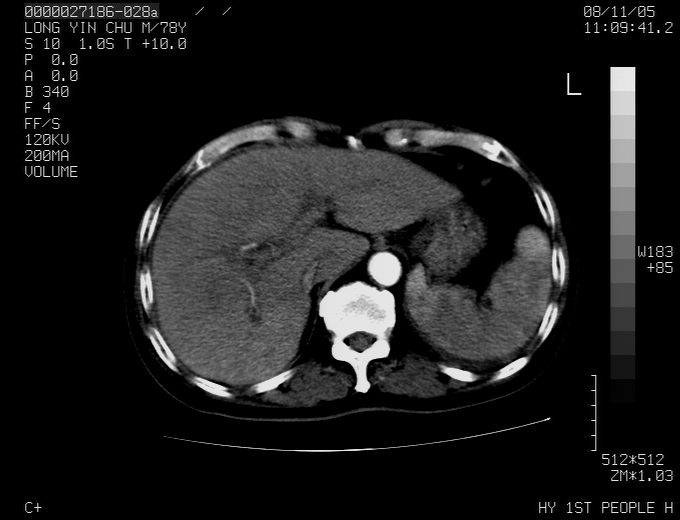

标题: CT16532:M78Y,肝脏病变,请会诊 [打印本页]

标题: CT16532:M78Y,肝脏病变,请会诊

腹胀,腹痛就诊,男性,78岁,外院b超未见异常。

肝ca,脾肾转移

考虑弥漫性肝癌并脾及双肾转移.双侧胸水.

图片质量欠佳:多考虑:左侧肾癌。脾脏转移!胸膜转移!

肝脾肾转移瘤可能性大,左肾不除外梗塞,双侧胸水

考虑弥漫性肝癌并脾及双肾转移,双侧胸水。